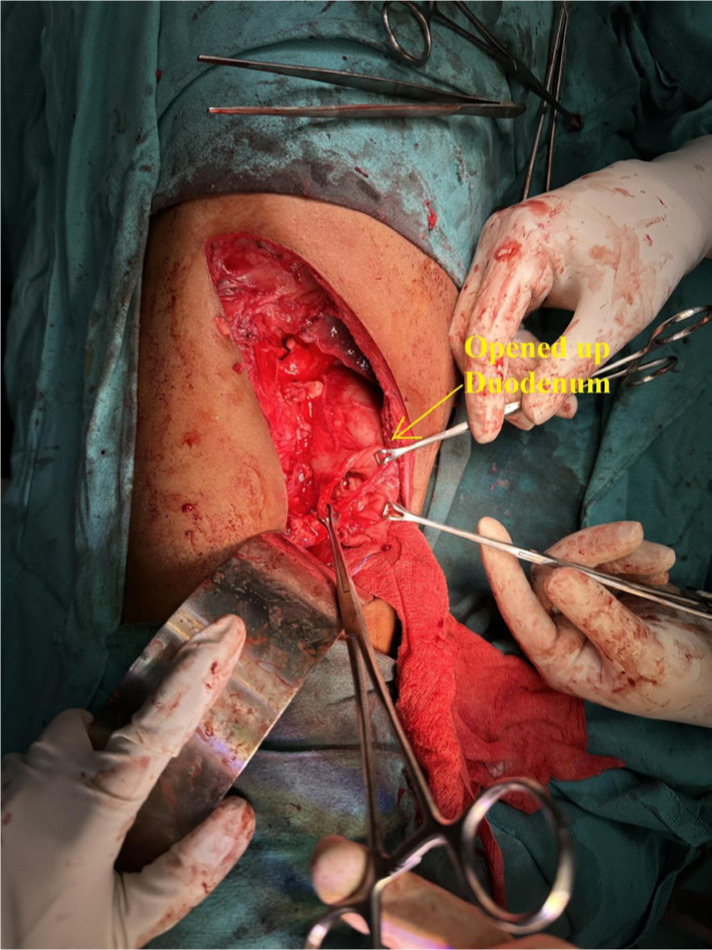

Germ cell tumor (GCT) is a neoplasm typically found in childhood, commonly originating from the testis or ovary. While there have been reported cases of GCT occurring in various extragonadal sites, primary intrarenal GCT is exceptionally rare. We present a case of 37-year-old male who presented with right upper abdomen pain. Imaging revealed a sizable mass within the right kidney. The patient underwent surgical resection of the renal mass during which there was perirenal infiltration into the duodenum and dense desmoplastic reaction all around. Subsequent histopathology confirmed the diagnosis of primary intrarenal nonseminomatous germ cell tumor (NSGCT). The patient underwent four cycles of adjuvant bleomycin, etoposide, and cisplatin (BEP) chemotherapy; at 6 months of follow-up, he is fine. The objective of this case report is to underscore the importance of considering NSGCT as a potential rare differential diagnosis in cases of renal neoplasms and further plan for the management.